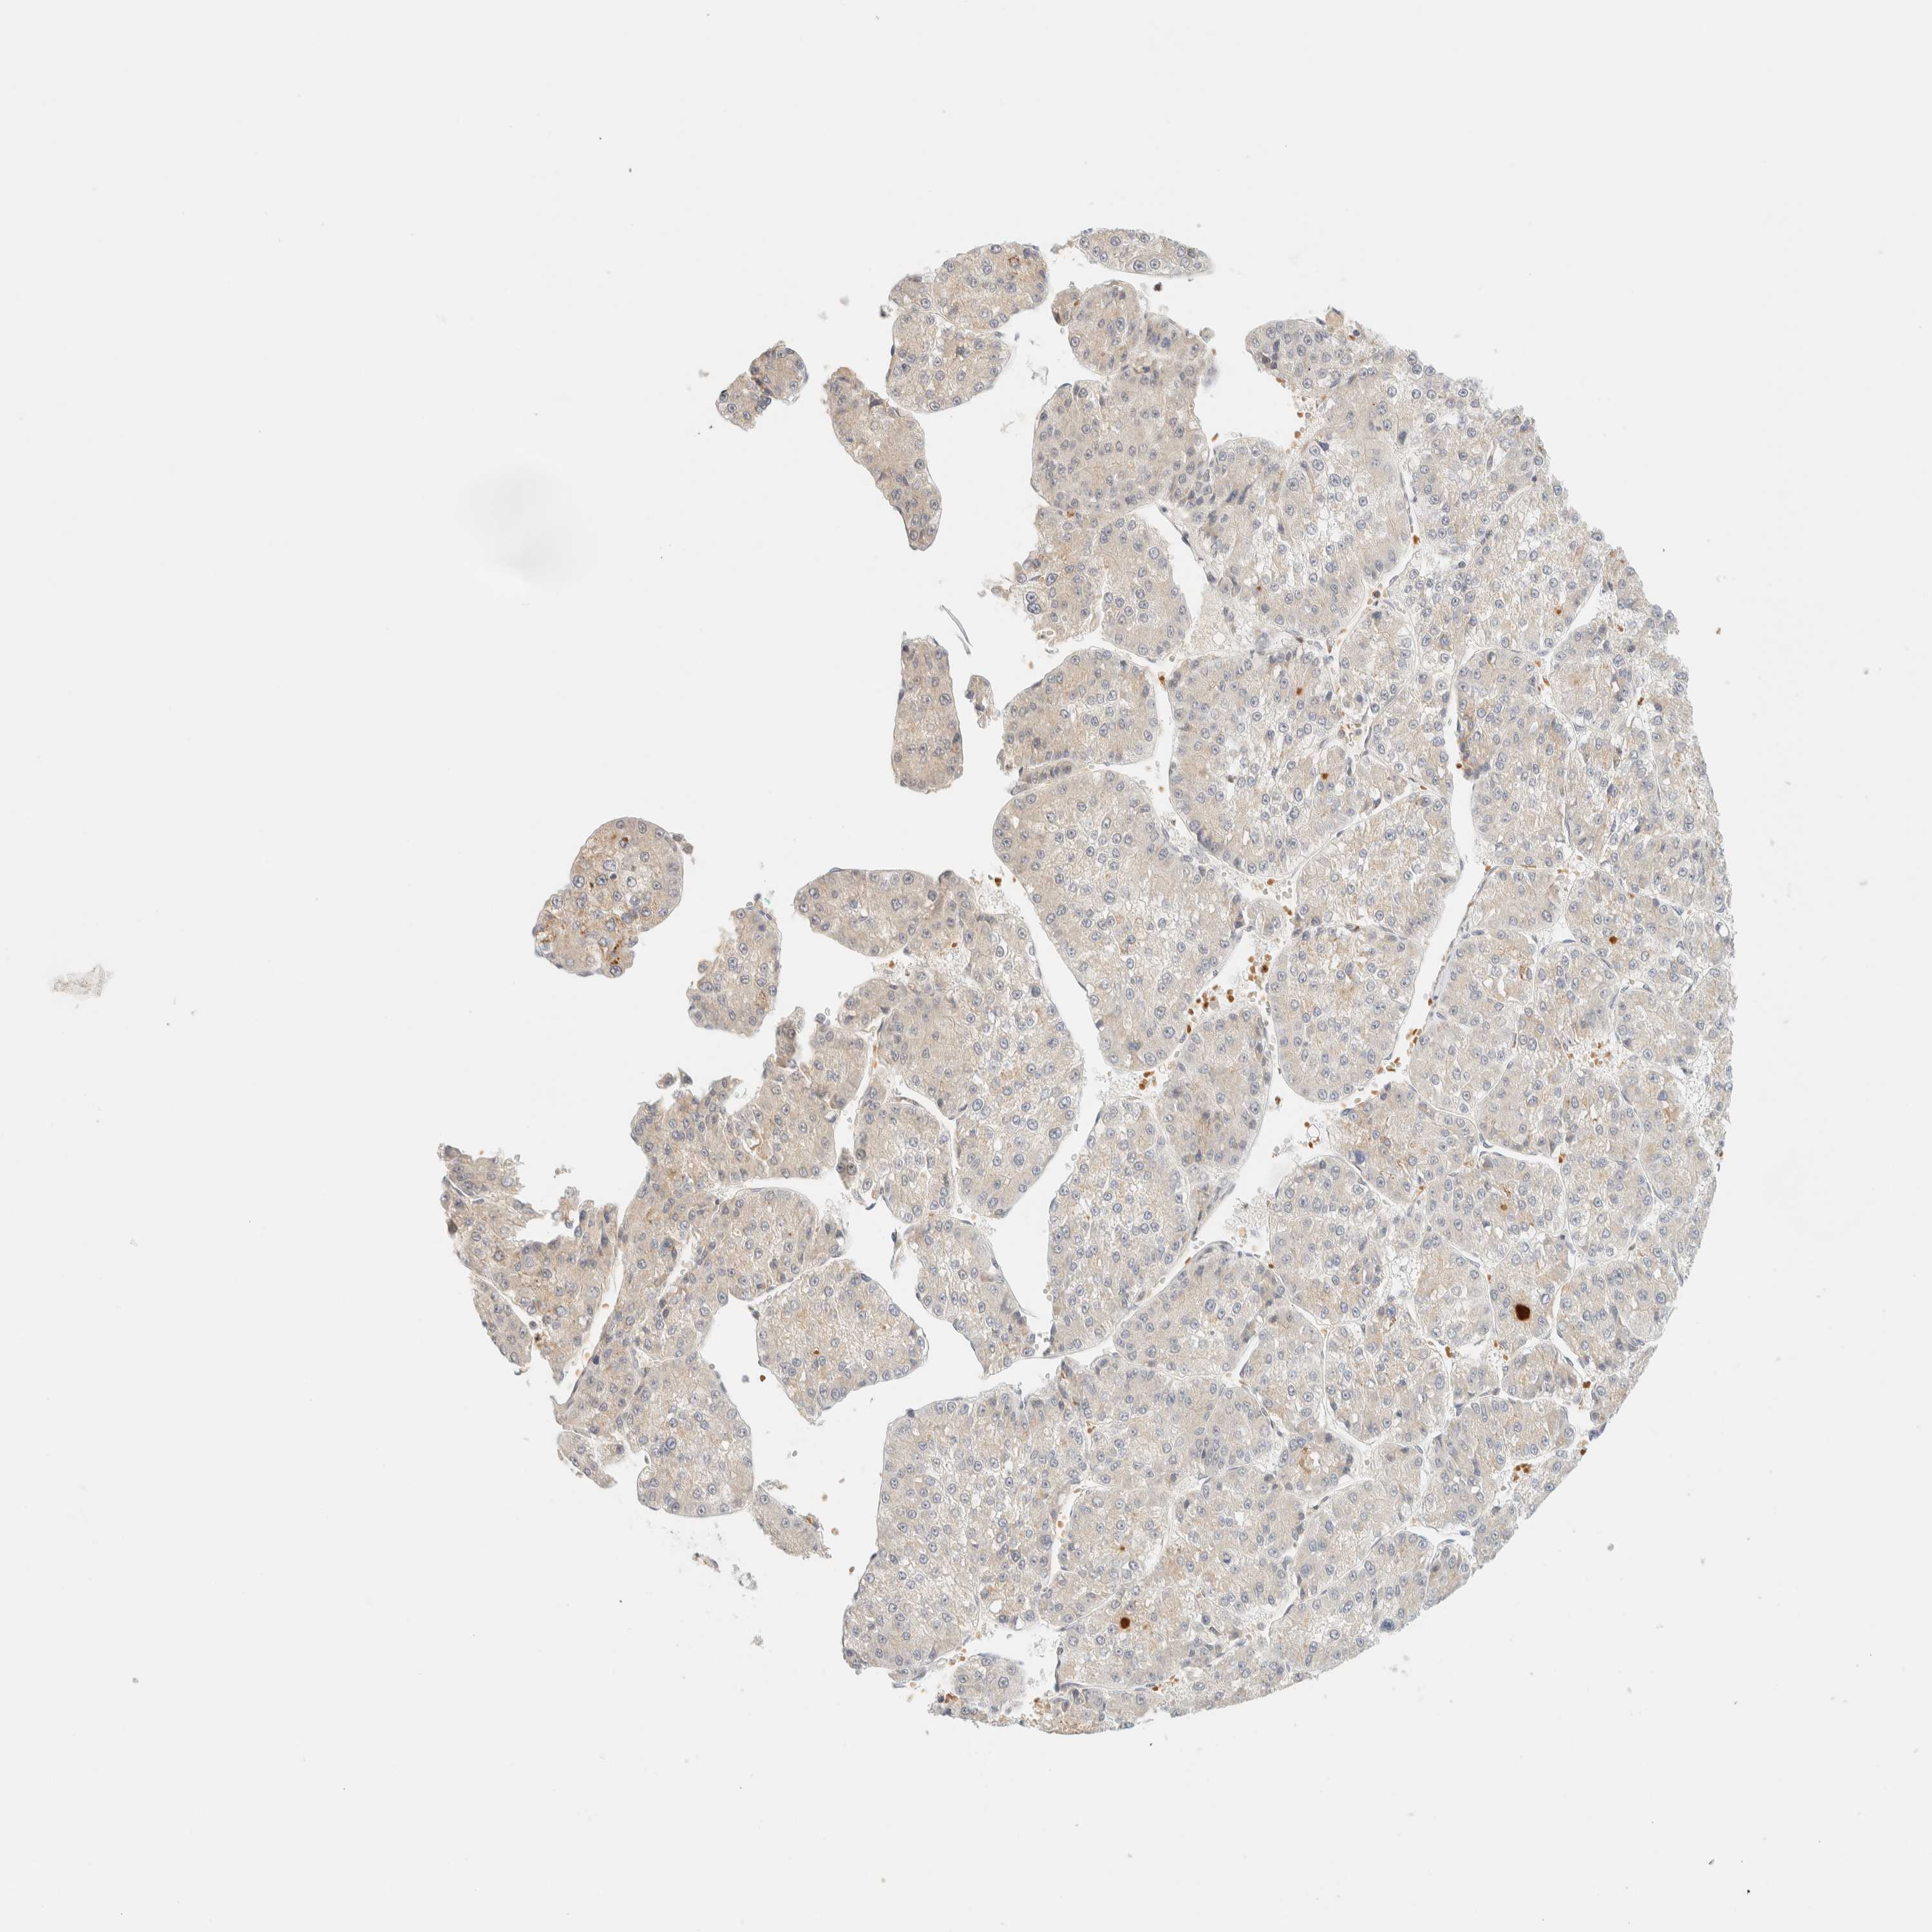

LIVER CANCER - Protein expressioni

A mouse-over function shows sample information and annotation data. Click on an image to view it in a full screen mode. Samples can be filtered based on level of antibody staining by selecting one or several of the following categories: high, medium, low and not detected. The assay and annotation is described here.

Note that samples used for immunohistochemistry by the Human Protein Atlas do not correspond to samples in the TCGA dataset.

Antibody stainingi

Antibody staining in the annotated cell types in the current human tissue is reported as not detected, low, medium, or high, based on conventional immunohistochemistry profiling in selected tissues. This score is based on the combination of the staining intensity and fraction of stained cells.

Each image is clickable and will lead to virtual microscopy that enables deeper exploration of all samples and also displays staining intensity scores, fraction scores and subcellular localization as well as patient and tissue information for each sample.

Antibody HPA012065

Staining

High

Medium

Low

Not detected

Intensity

Strong

Moderate

Weak

Negative

Quantity

>75%

75%-25%

<25%

None

Location

Nuclear

Cytoplasmic/membranous

Cytoplasmic/membranous,nuclear

Cholangiocarcinoma

Carcinoma, Hepatocellular, NOS